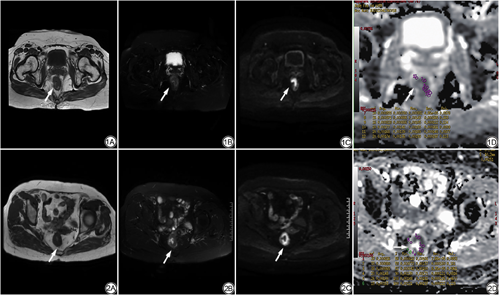

共纳入68例直肠癌患者,临床资料记录患者性别、年龄及肿瘤部位,详见表1。其中T分期T1~T2组30例、T3组38例,病理组织学分级低分化7例、中-高分化61例,LNM阳性22例、LNM阴性46例,TD阳性组13例、TD阴性组55例,LVI阳性组22例、LVI阴性组46例,见图1、2。